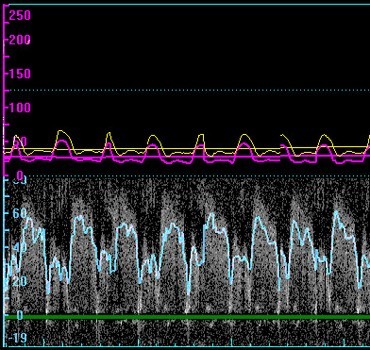

Through these awards, Dr. Banerjee has introduced a novel coronary diagnostic index, the so-called lesion flow coefficient, which seeks to fulfill the longstanding need for a quantitative parameter that enables simultaneous and combined assessment of pressure gradient, blood flow (Figure 2) and geometric information for any coronary stenosis.  Such an index would enable clinicians to make significant advancements in patient diagnosis and prognosis following percutaneous transluminal coronary angioplasty (PTCA) or bypass surgery by isolating the effects of epicardial stenosis from microvascular impairments.  This research has the potential to improve clinical decision making by using the lesion flow coefficient, and thus, improving on the guidelines for optimal patient care.

Heart monitor reading